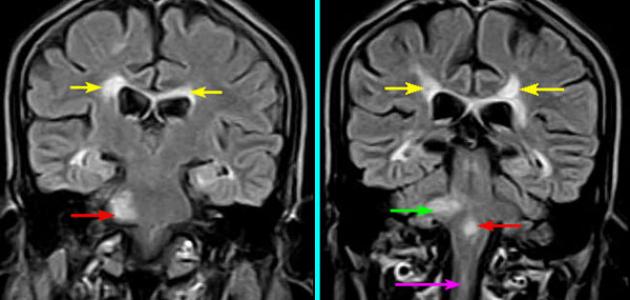

ضمور المخيخ

عمون - ضمور المخيخ هو حالة طبية تتميز بتقلص وتلف تدريجي في المخيخ، وهو الجزء الخلفي من المخ. يعتبر المخيخ مسؤولًا عن التنسيق والتحكم في الحركة والتوازن، بالإضافة إلى وظائف أخرى مهمة مثل التعلم والذاكرة.